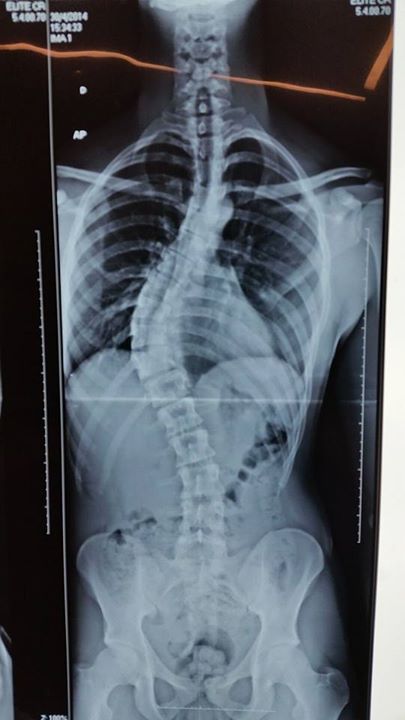

Imagens de pré e pós operatório de um caso de Escoliose:

Pré-operatório de Escoliose torácica em adolescente.